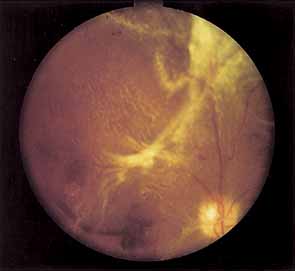

PROLIFERATIVE DIABETIC RETINOPATHY

Proliferative vessels usually arise from veins and often begin as a collection of fine vessels. When they arise on or within 1 disc diameter of the optic disc they are referred to as neovascularization of the disc (NVD) (Fig. 9). When they arise further than 1 disc diameter away, they are called neovascularization elsewhere (NVE) (Fig. 10). NVE nearly always grows toward and into zones of retinal capillary nonperfusion, but capillary nonperfusion is nearly always more widespread in eyes with NVD than it is in NVE.12 Interestingly, it is seen more often in patients younger than 40 compared to older patients with diabetes.13

Fig. 9 Advanced neovascularization of the disc.

Fig. 10 Neovascularization elsewhere (NVE).

Once the stimulus for growth of new vessels is present the vessels grow along the path of least resistance. The absence of the internal limiting membrane over the optic disc could explain the proclivity of new vessel growth at that location. Neovascularization grows readily along connective tissue scaffolding such as the posterior hyaloidal face (Fig. 11).